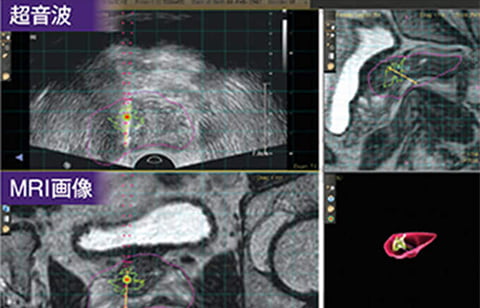

ウロナビとは?

MRIにて前立腺がんが疑われていても超音波にてその場所を特定できない時には、がんが疑われる部位を正確に穿刺(※)することが難しい場合がありました。そのため、前立腺生検の最中に、MRIでがんが疑われる場所を正確に示す技術が望まれてきました。その要望を満たすべく誕生したのが、UroNav(MRI超音波弾性融合前立腺生検装置)です。※ 穿刺(注射針を刺して、排出や注入すること)

ウロナビの特徴

事前に撮像されたMRIのT2強調画像を活用

MRIの画像を超音波画像に三次元弾性融合。

上段に超音波画像、下段にMRI画像をバラレル表示。

超音波画像で不明瞭な領域をMRI画像で即時確認可能超音波画像、MRI画像上に重心表示されたマーカーを狙うだけの簡単な生検が可能。

穿刺軌跡を3D化することで、生検結果の確認に対する視認性の向上と、穿剌軌跡をMRI画像に反映させることで穿刺結果と画像診断結果の検証が可能。